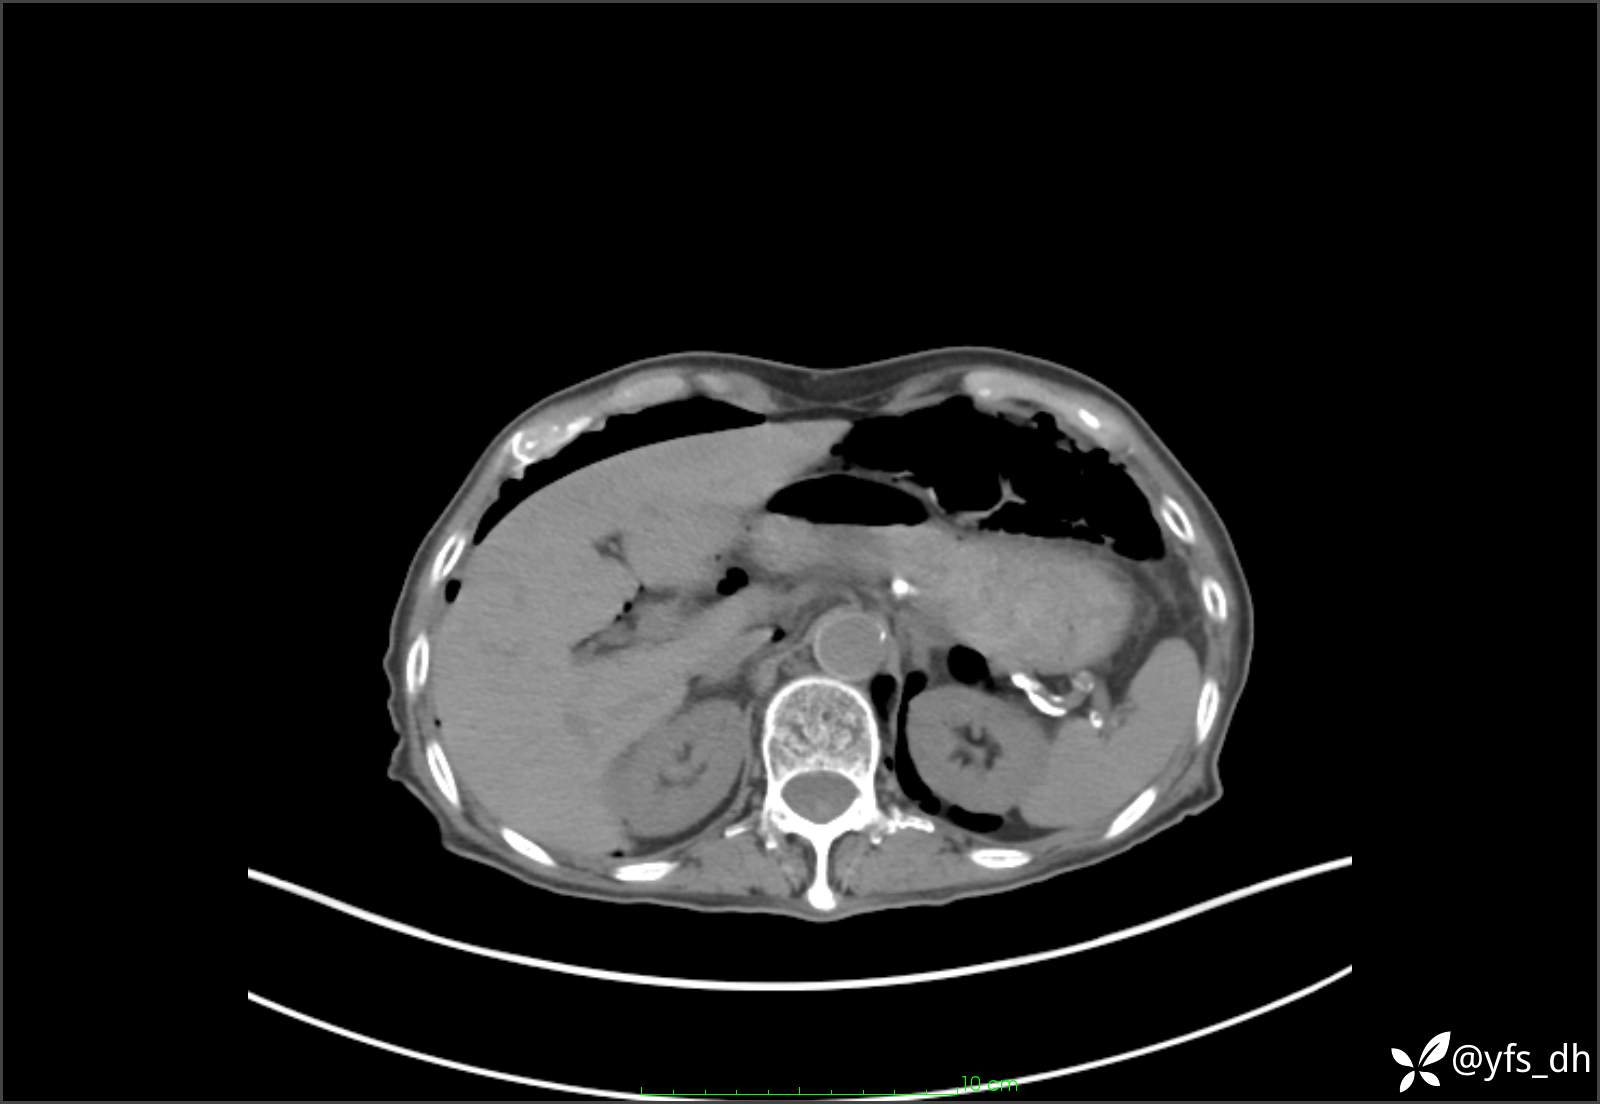

1.简要病史:患者4天前突发上腹部疼痛不适,但可以忍受。3小时前饭后突然加重,不能忍受后就诊。

2.简要手术记录:术中见腹盆腔大量肠液及粪便,乙状结肠中下段见一约3cm的破口。